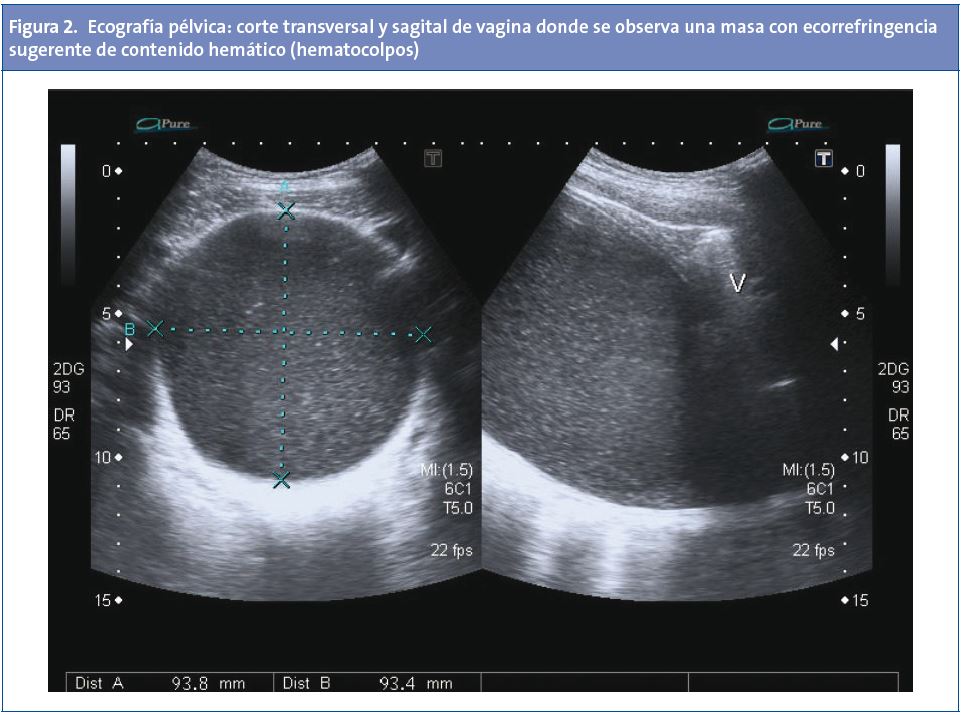

No refería fiebre, vómitos o molestias urinarias. Entre sus antecedentes personales destaca una criptomenorrea y estreñimiento habitual. Al explorar el abdomen se observó una tumoración en el hipogastrio que en la palpación se nota blanda, redondeada, no adherida y no dolorosa; desarrollo de caracteres sexuales secundarios estadio IV-V de Tanner. No se exploraron los genitales ni se hizo tacto rectal. Se derivó a Urgencias del hospital de referencia para hacer una valoración por el ginecólogo. A continuación se le hizo una analítica, que fue normal, un test de embarazo, un sondaje vesical, tras el cual persistía la tumoración, y una ecografia pélvica donde se vio una voluminosa lesión quística que ocupaba el hipogastrio por detrás de la vejiga y desplazando el útero cranealmente. Se demuestra continuidad con el cérvix, resultando compatible con hematocolpos; no se visualizó ninguna otra malformación genitourinaria asociada (Fig. 2).